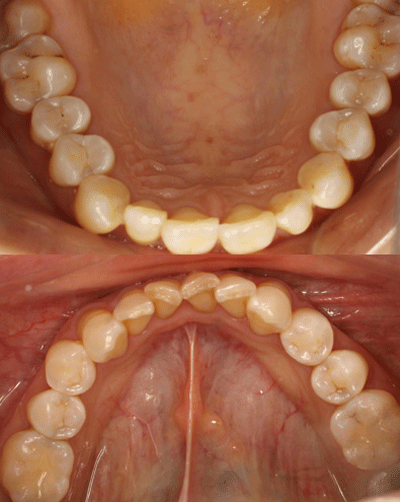

氟斑牙|瓷贴面修复——术前照片

术前上下颌照